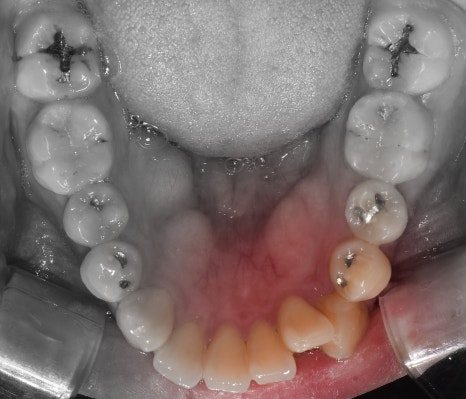

측면에서는 크게 2가지를 느낄 수 있습니다.

- 전치부 치아들의 치축, 전방 뻐드러짐

- 1치대 1치의 관계

*정상이라면, 1치대 2치의 관계를 가져야 됩니다.

또한, 측절치 및 송곳니의 총생들도 같이

관찰을 할 수 있습니다.

앞서, 1치대 1치 관계에 있던 교합관계들이

1치대 2치의 관계로 바뀐것을 볼 수 있으면서

길쭉하게 느껴졌던, U shape 형태의 악궁이

딱 보기 좋은, U shape 로 바뀌었죠.